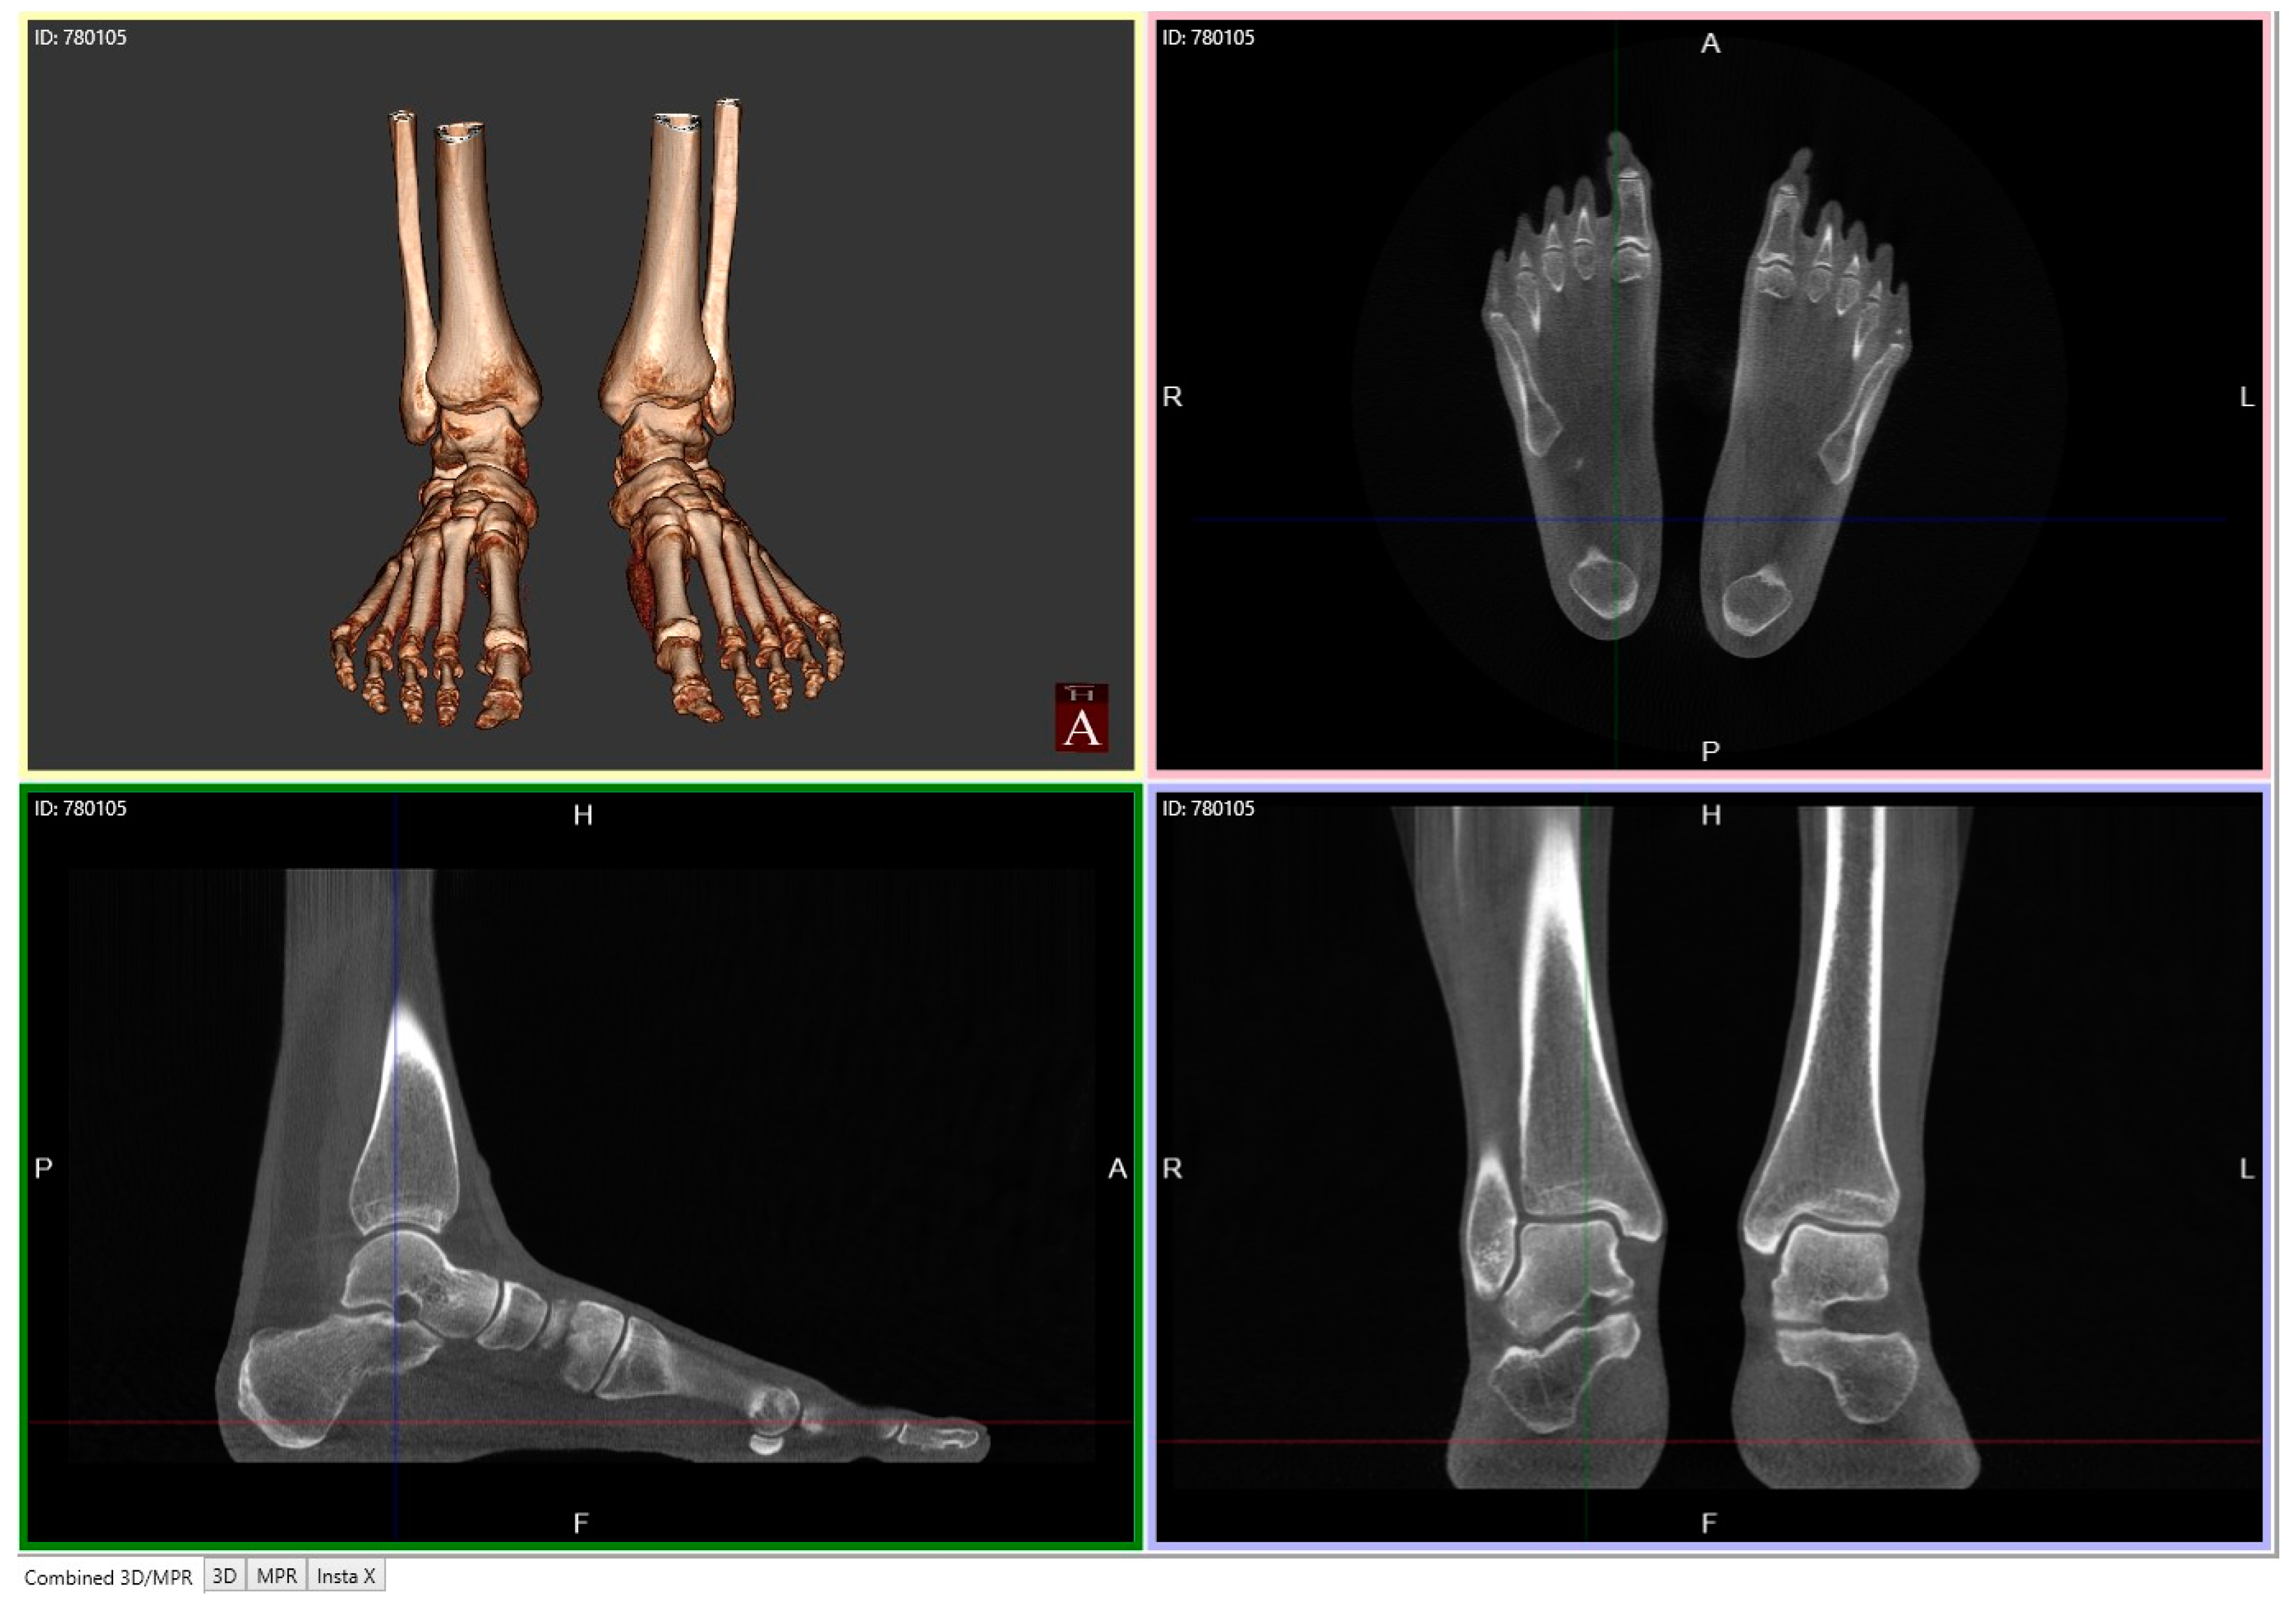

- 3D biometric techniques without segmentation

- 3D biometric techniques with segmentation (manual, semi-auto or auto)

4.2.1. Description of Techniques for Image Acquisition

4.2.2. Description of Advanced Computerized Techniques for Image Processing

Post-Processing

- Semi-Automatic 3D Biometrics